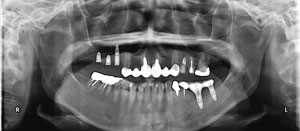

@K.K ‚³‚ñ@  72Î @—«@Žå•w      Žèp“ú@‚Q‚O‚O‚W”N@‚XŒŽ ‚X“úi‰Îj  ‰ºŠ{ƒm[ƒxƒ‹ƒKƒCƒhŽg—p@Ö¬“à’ÁÖ@•¹—p@

@@@@‰ºŠ{  All on ‚W@‘¦Žž‰×d

@@Rpl Tapered Rp‚SD‚O ~‚P‚O mm(‚S–{)@   Bmk MK‡V Rp‚RD‚V‚T ~ ‚WD‚T mm(‚R–{)       Bmk MK‡V Rp‚RD‚V‚T ~ ‚V mm